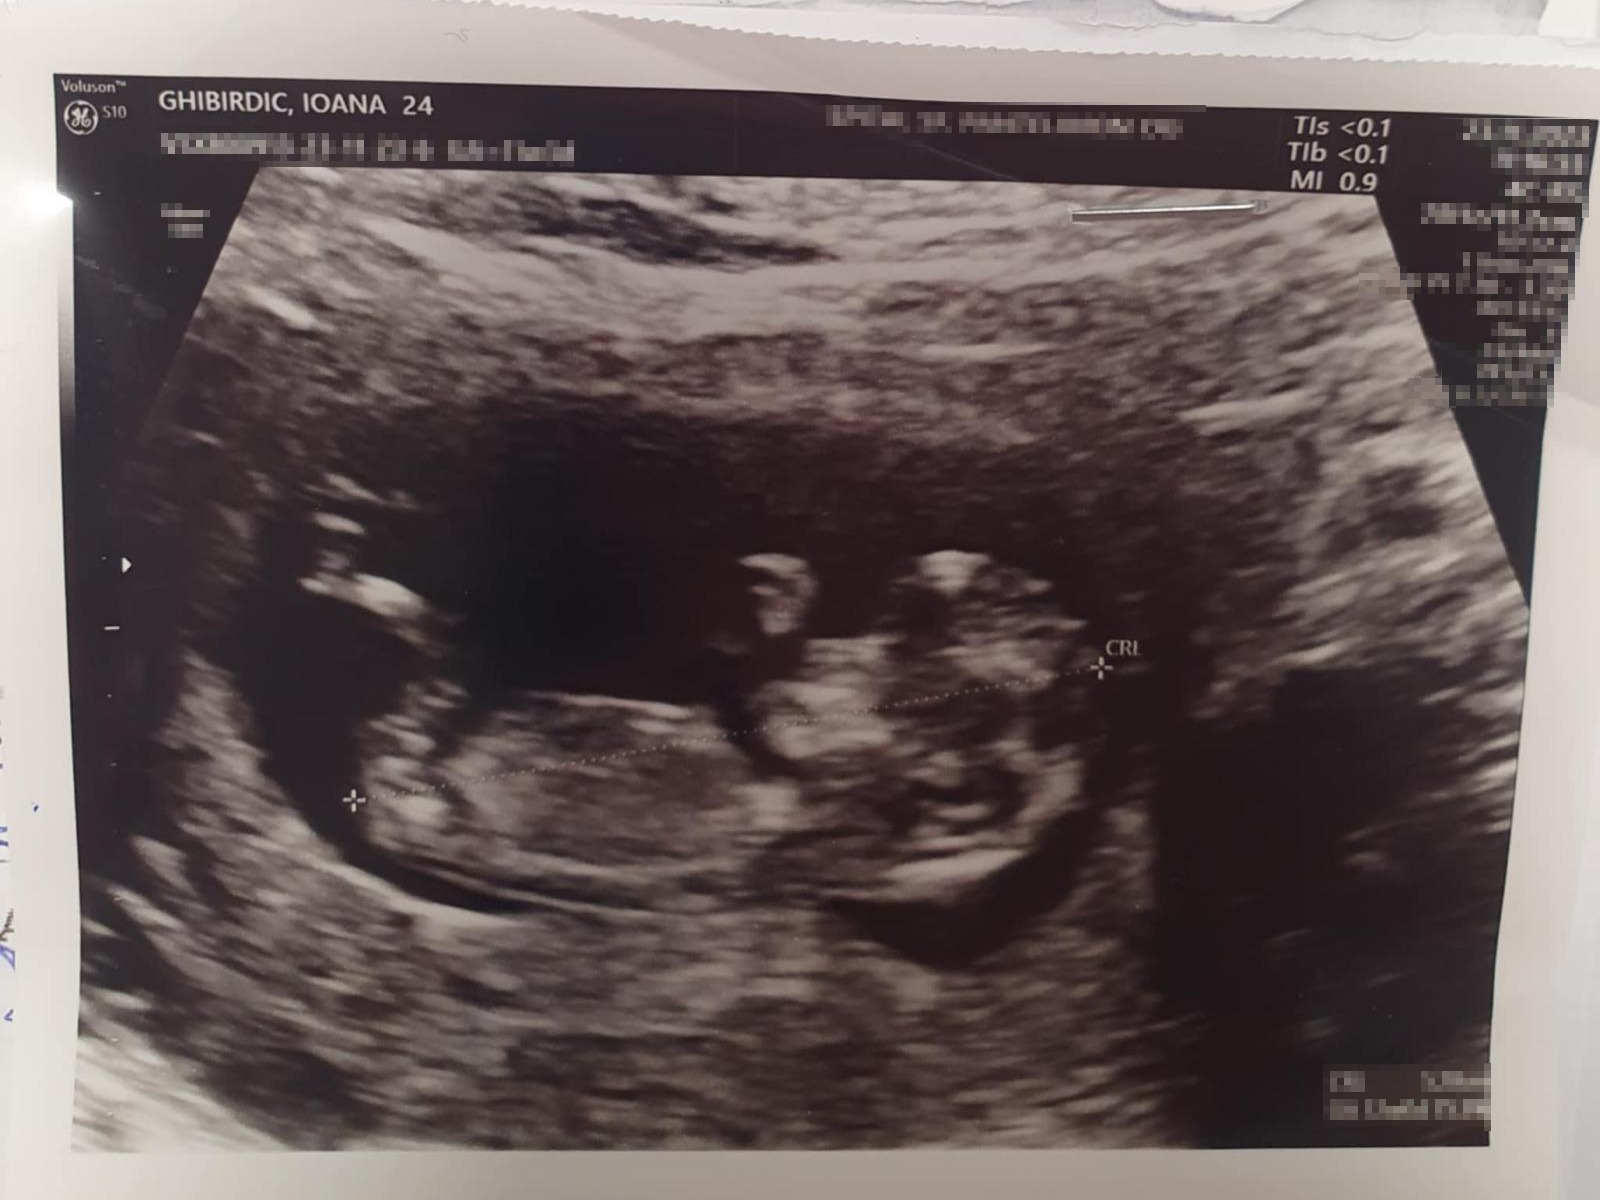

”Vor fi doi îngerași. Unul mai mare, fiind fata, pe care vom pune o fotografie și vom scrie ceva și unul mai micuț, fiind fetița, bebelușul, pe care o sa fie poză cu ecografie ei. Încă nu avem schița, dar am făcut demersurile necesare”, ne-a spus Mihaela Ghibirdic.

Crima care a avut loc pe 7 decembrie 2023 într-un magazin alimentar din cartierul Titan a șocat o țară întreagă. Paul Bușe, un bărbat de 72 de ani, tatăl patroanei magazinului, a ucis-o cu sânge rece pe una dintre vânzătoare. Ioana Beatrice avea 24 de ani și era însărcinată în 4 luni, urmând să aducă pe lume primul ei copil.